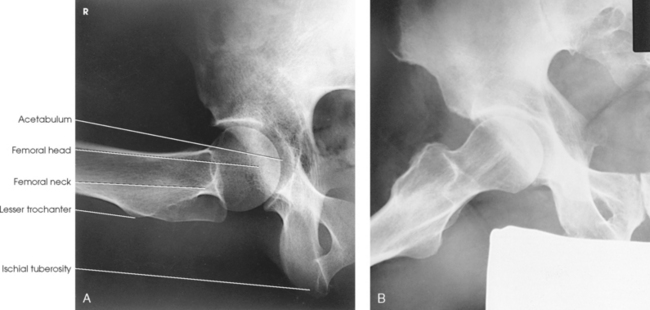

The femur is the longest, strongest, and heaviest bone in the body. The proximal end of the femur consists of a head, a neck, and two large processes: the greater and lesser trochanters (Fig. 7-4). The smooth, rounded head is connected to the femoral body by a pyramid-shaped neck and is received into the acetabular cavity of the hip bone. A small depression at the center of the head, the fovea capitis, attaches to the ligamentum capitis femoris (Fig. 7-5; see Fig. 7-4). The neck is constricted near the head but expands to a broad base at the body of the bone. The neck projects medially, superiorly, and anteriorly from the body. The trochanters are situated at the junction of the body and the base of the neck. The greater trochanter is at the superolateral part of the femoral body, and the lesser trochanter is at the posteromedial part. The prominent ridge extending between the trochanters at the base of the neck on the posterior surface of the body is called the intertrochanteric crest. The less prominent ridge connecting the trochanters anteriorly is called the intertrochanteric line. The femoral neck and the intertrochanteric crest are two common sites of fractures in elderly adults. The superior portion of the greater trochanter projects above the neck and curves slightly posteriorly and medially.

Structures shown: The image shows an AP projection of the pelvis and of the head, neck, trochanters, and proximal one third or one fourth of the shaft of the femora (Fig. 7-18).

Structures shown: The resulting image shows the head, neck, trochanters, and proximal one third of the body of the femur (Fig. 7-31). In the initial examination of a hip lesion, whether traumatic or pathologic in origin, the AP projection is often obtained using an IR large enough to include the entire pelvic girdle and upper femora. Progress studies may be restricted to the affected side.